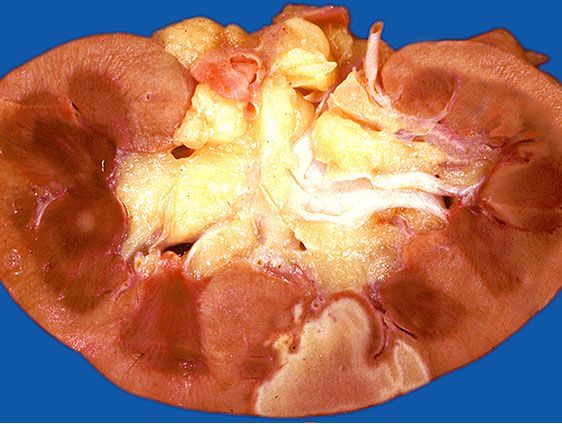

If the body is unable to regenerate after an injury, repair leads to scarring

Scarring occurs in cases where injuries are severe (disrupting stem cells and/or tissue architecture), or the regenerative capacity of the damaged organ is low

Examples of this process include things like deep lacerations (that leave a scar!), infarcts, and cirrhosis (fibrosis of the liver due to longstanding injury)